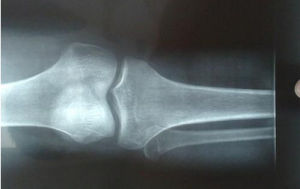

簡介 部位 病因 症狀 表現及診斷骨骺線閉合,是骨骼發育的一個過程。骨骺與乾骺端之間的軟骨,在幼兒的x光片上表現為一條較寬的透光帶,它隨著年齡的增長而逐漸變短,當骨骺與乾骺端的軟骨完全骨...

內容骨骺線是指骨骺板的截面影像,骨骺與乾骺端之間的軟骨,在幼兒的x光片上表現為一條較寬的透光帶,它隨著年齡的增長而逐漸變短,當骨骺與乾骺端的軟骨完全骨化後,...

兒童的四肢長骨幹骺端與骨骺之間有一盤狀軟骨結構,稱為骺板。

骨骺和骺板都是未成熟的四肢長骨的生長區域,也是兒童骨骼的最薄弱和最易骨折的部位。